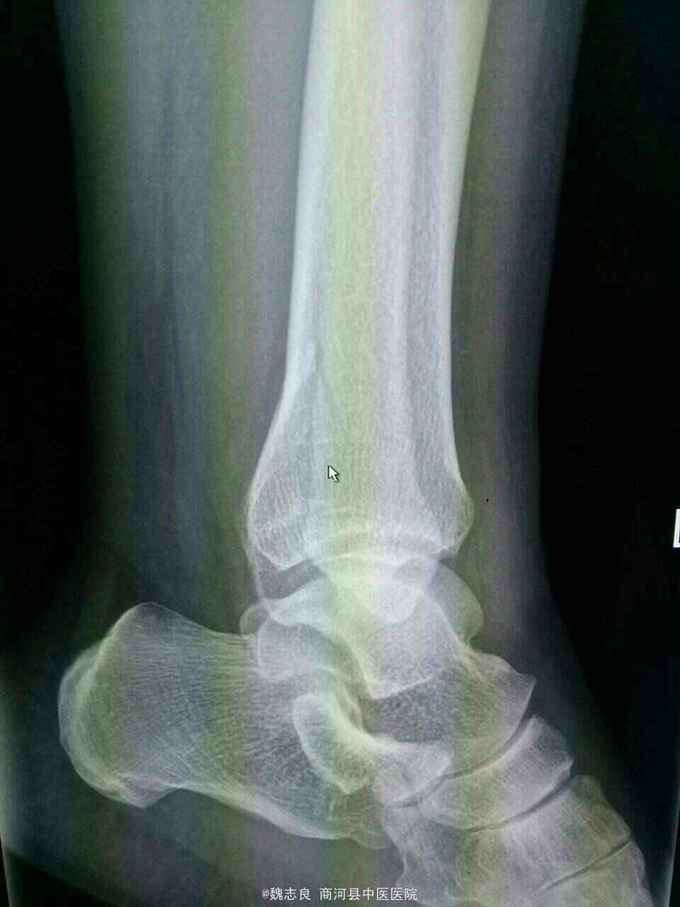

X线表现:正位像未见骨折征象,侧位像左外踝骨折。CT证实为内踝骨折。提醒我们关节内的骨折以及高度怀疑骨折的患者应该做ct检查,避免漏诊。